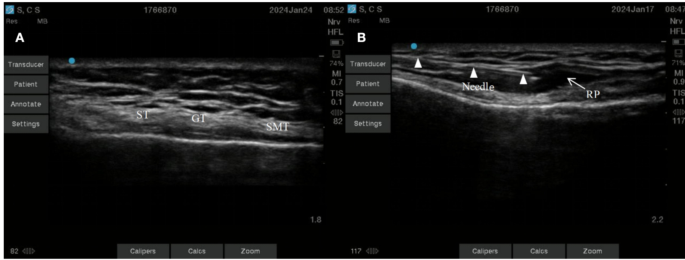

Pes anserinus tendon block

The patient lies in a supine position with the knee slightly bent. The high-frequency linear array probe is placed obliquely along the long axis on the inner side of the knee joint cavity, with the upper edge of the ultrasound probe rotated approximately 20° towards the patella. The high-echogenic medial femoral condyle and tibial plateau are visible, and the dense high-echogenic medial collateral ligament of the tibia covers the triangular medial meniscus, At this time, slowly move the ultrasound probe downwards while rotating it clockwise (for the right knee) or counterclockwise (for the left knee) until the tendons of the pes anserinus (sartorius tendon, gracilis tendon, semitendinosus tendon) are visible on the ultrasound image (Fig. 2A) crossing the medial collateral ligament, Using the in-plane needle insertion technique, a 22G nerve block was injected through the lateral end of the probe into the skin, reaching the target location of the surface of the gracilis and semitendinous tendons (Fig. 2B). It can be seen that the local anesthetic solution diffuses fully on the tendon surface.